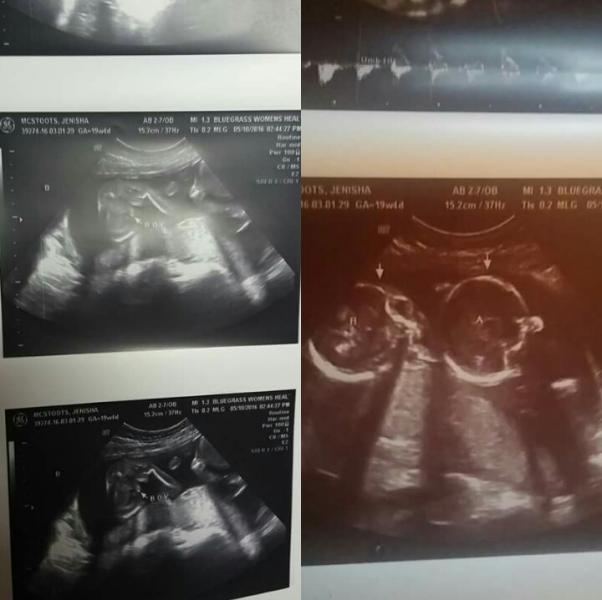

I had an appointment today with my OB, it was just supposed to be a gender scan to reveal my baby gender...It did reveal that I do have a son but I am having twins 👶👶 I had an initial scan done at 9 weeks 4 days (picture in comment) where only one baby was seen... don't know how that happened. But I am having twins and one is a boy 💙 the second had legs crossed the whole time 💛 so we shall see. This was big news I am 20 years old and pregnancy news was shocking enough! But I will do the best by my twins! They are who I was blessed with and I'm thankful.